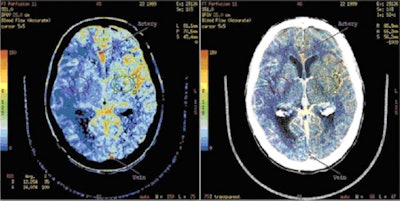

![]() |

| Toshiba's whole-brain perfusion images in stroke patients. CBF = cerebral blood flow, CBV = cerebral blood volume, and MTT = mean transit time. Image courtesy of Toshiba. |